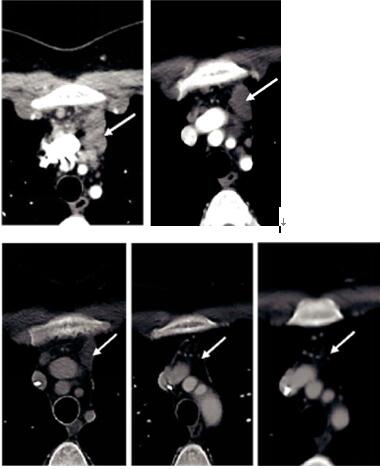

患者出现发热和寒战,并发生皮疹,但是当dabrafenib剂量降低至75 mg / d后,病人迅速改善。 治疗1个月后CT扫描,具有显著的影像学变化,纵隔淋巴结肿大缩小,没有新的肝或纵隔病变(图1A和B和2A和B与图1C和2C),并且在3个月时的影像学检查显示出纵隔淋巴结肿大和肝脏局部病变进一步缓解(图1D和2D)。 8个月的影像显示纵隔淋巴结持续缩小,肝脏病变完全消退(图1E和2E)。 患者目前仍继续进行治疗。

图1:ABCDE